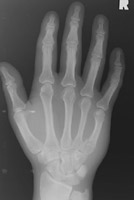

- Click on the image for a larger versionDPA radiograph of a fracture of the second metacarpal.